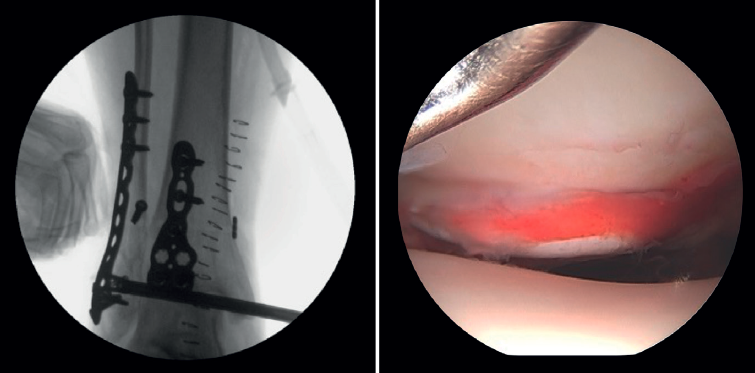

2. Reducción abierta y fijación interna del maléolo lateral y/o medial

La artroscopia asiste a la RAFI para evaluar la congruencia de la superficie articular. Es especialmente útil para la reducción del maléolo medial. La tasa de mal reducción en fracturas del maléolo medial es del 22,2 al 32,6%(15,16). La artroscopia inicial permite valorar si la reducción del maléolo tibial puede realizarse de forma abierta o cerrada. En casos con desplazamiento significativo, se opta por una síntesis abierta, manteniendo siempre control artroscópico durante el procedimiento para asegurar una reducción precisa y evitar la rotación del fragmento distal (Figura 4).

Xie mostró que la estabilización de la sindesmosis con un sistema de fijación dinámico ofrece resultados funcionales equivalentes y menos complicaciones en comparación con la fijación con tornillos(28). La RAFIAA permite evaluar la congruencia articular tras la reducción anatómica tanto de la sindesmosis posterior como de la sindesmosis anterior. Permite también evaluar la sobrecorrección que puede producirse al comprimir en exceso la mortaja, que ha demostrado ser muy artrogénica(29). Durante la reducción de la sindesmosis nos ayudamos de un palpador que deberemos poder introducir una vez fijada la sindesmosis.